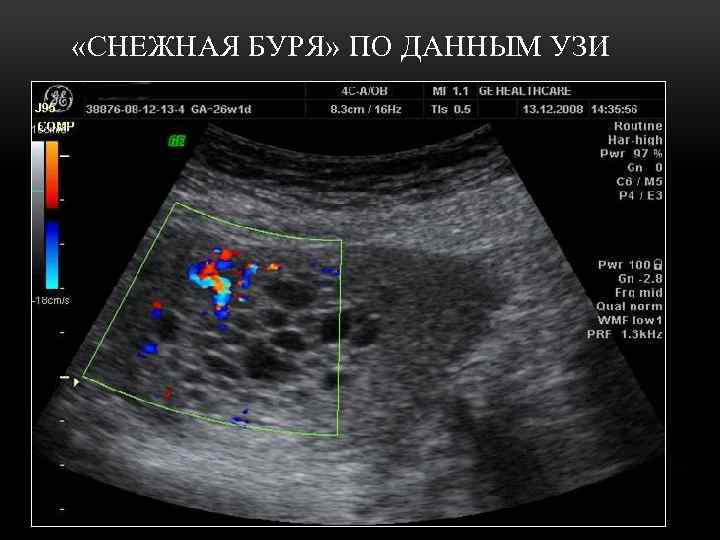

ДИАГНОСТИКА ПУЗЫРНОГО ЗАНОСА • Оценка клинических симптомов во время беременности • Ультразвуковое сканирование органов малого таза • Определение сывороточного уровня бета. ХГЧ (при нормальной беременности пик ХГ — в 9 -10 нед, не выше 150000 м. МЕ/мл, с последующим снижением уровня)

«СНЕЖНАЯ БУРЯ» ПО ДАННЫМ УЗИ